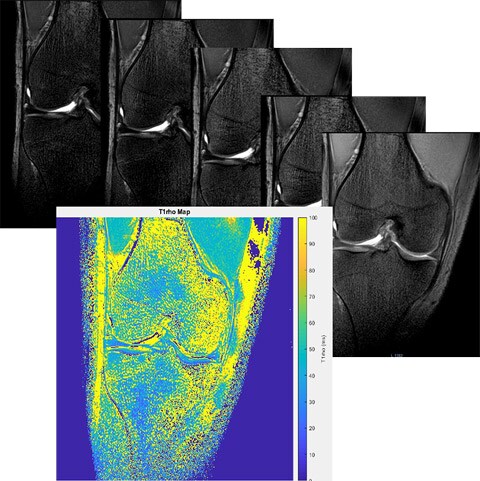

Цель Изучить релаксационные показатели Т2, Т1rho-картирования хрящевой ткани суставной поверхности коленного сустава, как количественный критерий выраженности патологий различного характера. Описание проекта Дегенеративные изменения суставов в зависимости от возраста, величины физической нагрузки, в том числе массы пациента, а также сопутствующих заболеваний приводят к изменениям биохимических процессов в хрящевой ткани. Стандартный МРТ протокол позволяет создать достаточный контраст для выявления морфологических изменений в гиалиновом хряще суставной поверхности. На данный момент самым распространенным методом оценки тяжести острых и хронических повреждений суставного хряща из-за своей простоты получили системы классификации, предложенные Outerbridge (1961), Jackson (1988) и Yulish B.S. et al. (1987). Такой подход крайне эффективен в оценке степени хондромоляции, однако не отражает нарушения биохимических изменений в выявленных очагах и зонах поражения гиалинового хряща. Значения релаксационных параметров Т2, Т1rho, получаемых методиками количественной МРТ (qMRI), связаны с физическими свойствами, а также с водным и коллагеновым составом внеклеточного матрикса хряща коленного сустава. Исследование изменения этих параметров при различных заболеваниях, травмах и иных факторах позволит построить точные биофизические модели повреждения хряща, а также потенциально разработать количественные методы определения стадии хондромоляции. Задачи Создание и оптимизация быстрых протоколов сканирования, а также процесса обработки таких изображений для получения Т2 и T1rho карт хрящевой ткани коленного сустава. Получение релаксационных показателей хрящевой ткани суставных поверхностей на примере коленного сустава, в зависимости от степени хондромаляции в разных группах пациентов.

Результаты Разработаны оптимальные протоколы сканирования для получения карт Т2 и Т1rho гиалиновой хрящевой ткани коленного сустава. Проведены измерения значений Т2 хрящевой ткани суставной поверхности коленного сустава у пациентов с рассекающим остеохондритом, а также влияние индекса массы тела на параметры Т2. Результаты представлены на конгрессах: РОРР 2019, Радиология 2018, Радиология 2017

Процесс получения T1rho карт.